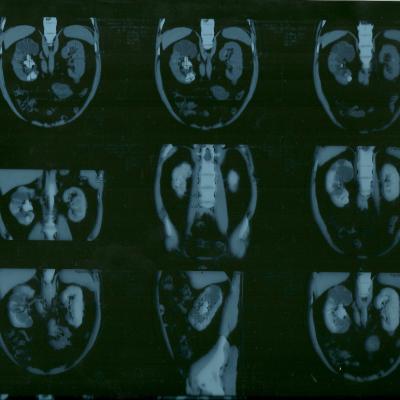

коралловидный камень

Морозов Алексей. Здравствуйте,находился

на лечении в урологическом отделении

г.Йошкар-Ола по поводу МКБ, В правой почке

обнаружен коралловидный камень,врач

рекомендовал ЧПНЛ в Нижнем Новгороде,но